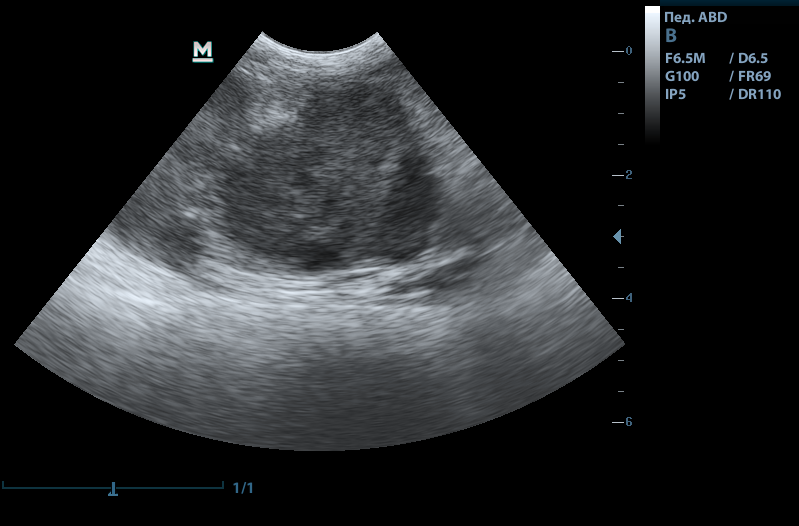

На мониторе появляется увеличенное изображение органа. При необходимости врач может воспользоваться функцией многократного увеличения и тщательно рассмотреть структуру органа.

Что показывает УЗИ желудка

На УЗИ желудка можно изучить состояние и структуру внутренних органов, оценить перистальтику (двигательную активность стенок), толщину стенок органа, полость и ее содержимое, состояние окружающих тканей. Также во время исследования проводится оценка наполнения желудка — присутствие газов или свободной жидкости. Дополнительно можно исследовать желчный пузырь.

Диагноз: Утолщение стенки антрального отдела до 7 мм, сохранение слоистой структуры, замедленная эвакуация содержимого. Диагноз: хронический антральный гастрит с нарушением моторики.

Что дало УЗИ: УЗИ подтвердило воспалительный процесс в желудке и исключило опухоли, инородные тела и обструкции. Это позволило назначить целенаправленную терапию: прокинетики, гастропротекторы, гипоаллергенную диету.